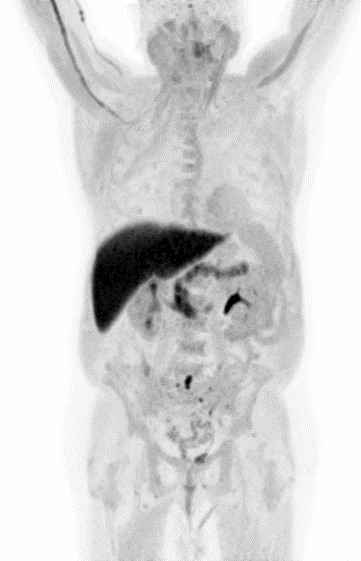

Partial nml and melanoma PET scan

The goal of PET/CT imaging in oncology is to enable the physician to distinguish between benign and malignant pathologies, to determine the extent of disease, to detect residual and recurrent tumors, to monitor the effectiveness of treatments, and to guide therapies.